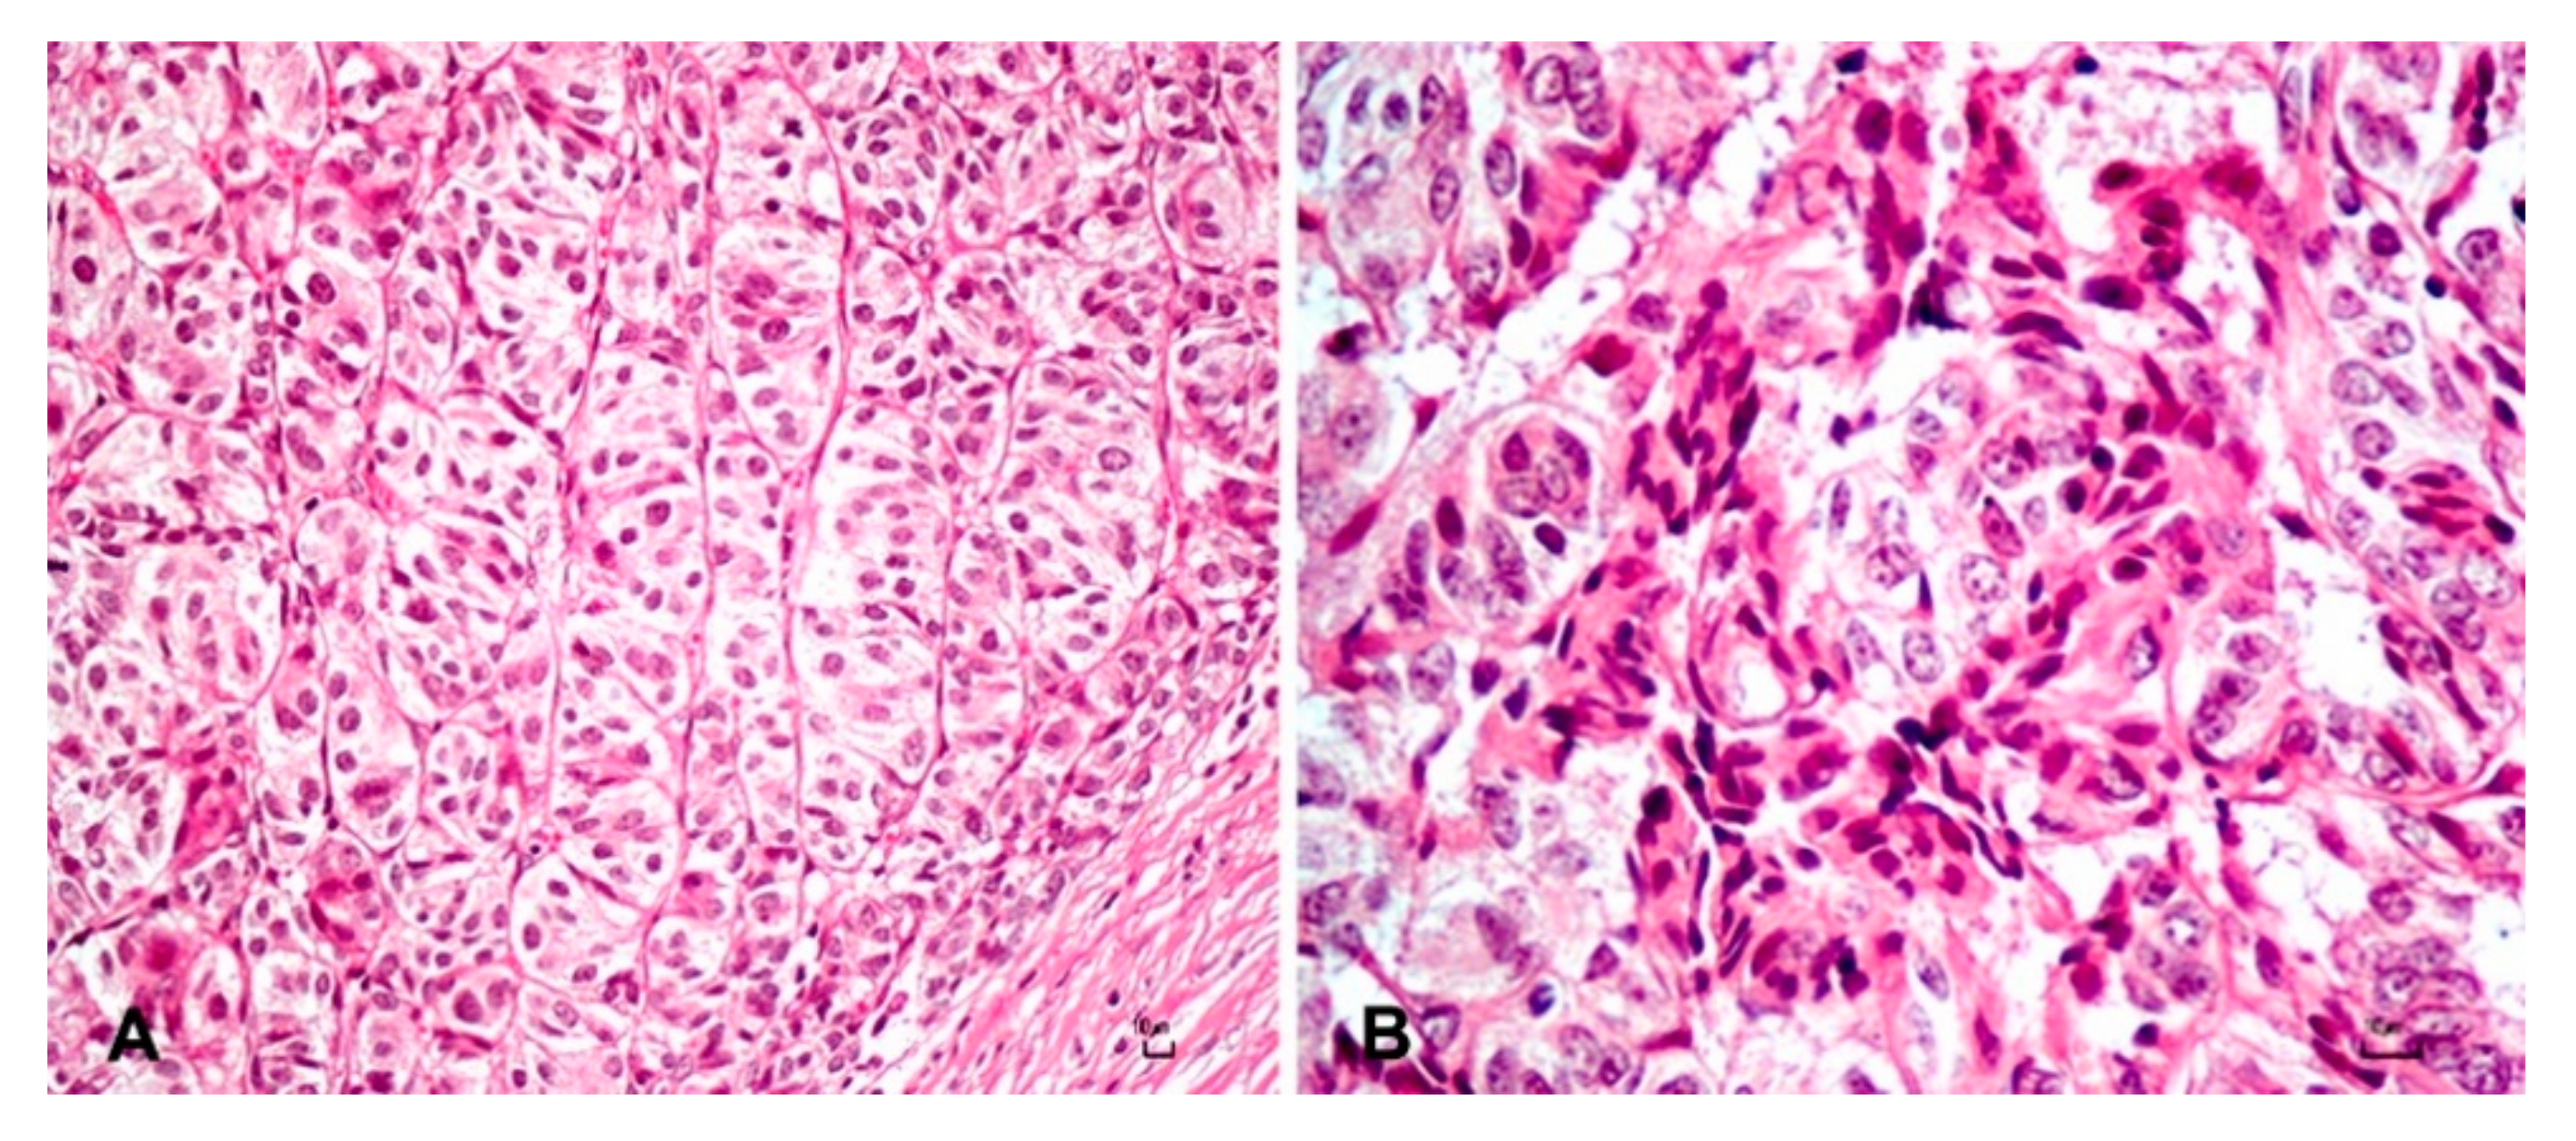

3. Results